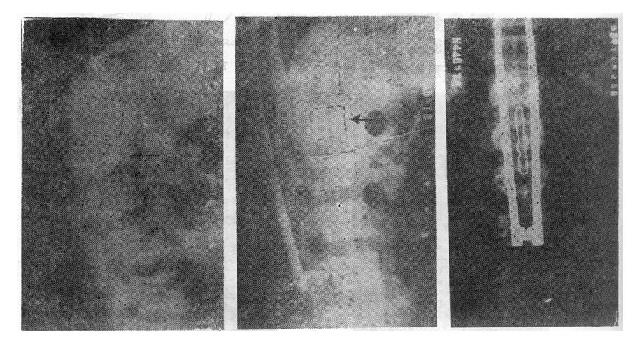

(三)爆裂型骨折的治疗 如不合并严重的神经系统症状,损伤又在两周以内者,可以用双Harrington法,撑开矫正,或用Dick手术;可以获得满意的结果(图73-13)。复位后需融合相邻两个椎间隙,因为CT常显示在爆裂型骨折中,相邻的上、下两个椎间盘均有损伤,如不融合,日后取棍后会出现腰痛。使用本法时,如前纵韧带完整,则很容易恢复椎体前方的高度。但爆裂型骨折存在下述三种情况时,需行前路减压术:①合并神经系统症状较重者;②就诊较晚,已两周以上者(常常10天以上就复位比较困难);③脊柱CT扫描显示已有较大的骨折片突出椎管内,使髓腔管变窄超过30%以上者,预示后纵韧带已有明显损伤,使用后路手术方法已无法使骨折片复位。Kostuik复习了日本和多伦多治疗脊柱骨折的结果后证实,前路减压术能使膀胱、肛门及肢体功能得到更好的恢复。

图73-13 爆裂型骨折的治疗 ①术前,骨折脱位;②术后,侧位;③术后,正位

前路手术方法为病人取侧卧位,腰椎骨折由肾切口进入,胸腰段骨折则经切除第10肋之胸腹联合切口进入,结扎节段血管后,切开并向侧方推开椎前胸膜壁层,从腰椎侧方向椎体前方剥离骨膜,先掀起骨膜再进行骨折的处理,有助于防止血管损伤。然后切除骨折处的椎间盘,此时先找出椎间孔前缘,保护好神经和脊髓,再用咬骨钳咬除病椎骨质(保留作植骨用),靠后部分可用电钻磨(图73-14之①②)。对于旋入椎管腔内的骨片,可用刮匙将骨片旋转回原来的部位,减除脊髓的压迫(图73-14之③)。直至看到对侧硬脊膜,然后进行植骨。取一段腓骨嵌入植骨,在一助手将脊柱由后向前推顶的同时,将腓骨卡入,恢复椎体前缘高度(图73-14之④)。然后在植骨块的两侧再植入一些松质骨。

图73-14 前路手术治疗旋转型脊柱骨折

①剥离骨膜②咬除病椎骨质;③使骨片复位;④植骨